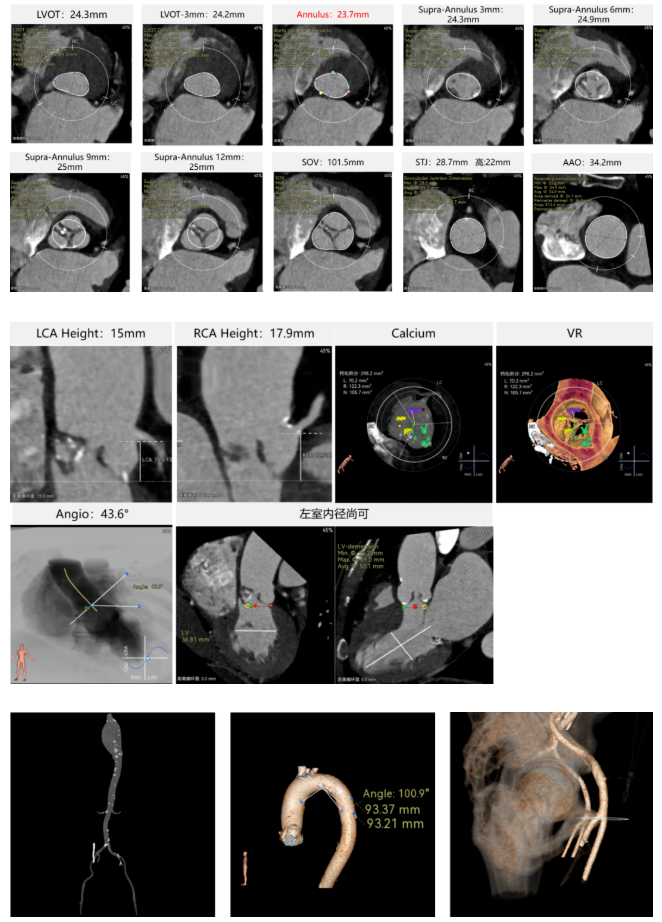

患者病史 术前超声提示:主动脉瓣退行性病变;中-重度狭窄并轻度返流;中-重度三尖瓣返流;中度肺高压 术前CT 三叶瓣,瓣叶增厚轻度钙化,右无交界有粘连,预计可以扩开,主动脉根部直径23.7mm,LVOT直径24.3mm,呈直筒型;双侧冠脉开口高度可,瓣叶长度小于冠脉开口上缘到主动脉根部的距离;窦部空间可,STJ、升主动脉内径可;主动脉水平夹角43.6°,非横位心;主动脉弓角、弓距可,左室内径可;外周入路无明显迂曲,有零星散状钙化,双侧股动脉内径可,均能通过20F大鞘,右股低分叉。 手术策略 推荐右侧股动脉为主入路使用20F大鞘,左侧股动脉为辅入路,右股分叉上方1cm穿刺;推荐使用22mm球囊预扩,预装AV26瓣膜,备AV29瓣膜,初始定位为真实瓣环上方3mm,瓣膜释放过程中释放张力使其自然下滑,工作位观察瓣膜稳定性,最终理想位置为零位;左右重合位:RAO23°CAU32°;右窦居中位:LAO5°CAU12°;左冠切线位:LAO34°CRA14°。 手术过程 术中右股动脉痉挛,内径变为3.8mm,遂更换左腋动脉入路;18球囊预扩,后植入AV26 ProStyle A®瓣膜;瓣膜精准释放于目标位置,超声显示无明显瓣周漏,血流动力学即刻改善。 术中右股动脉痉挛,内径变为3.8mm,更换左腋动脉 主动脉根部造影 18球囊预扩 初始定位 工作位观察 术后即刻表现:无瓣周漏,术后峰值压差10mmHg 术后3天复查超声峰值压差14mmHg Prostyle A®预装干瓣——助力临床最优化解决方案: 轻松过弓,精准可控:该病例经左腋动脉入路,输送系统较细的尺寸+柔顺的输送系统通过性能得到了很好的验证; 释放稳定:平衡的径向支撑力降低了释放过程中的张力,流入端小锥角设计能够迅速锚定贴边,80%可回收使得观察位和释放后的位置差距减少,大大提高了释放过程中的精准性,能够轻松应对高难度病例; 预装干瓣 便捷顺安:金仕生物专利抗钙化技术运用纳米技术去除组织内的细胞碎片和磷脂,封闭游离醛基,从根本上阻断了瓣膜钙化的多项因素,显著提升了瓣膜的耐久性;同时,相比较传统戊二醛保存方式,干式存储最大限度的保留心包的亲水亲油平衡,还原组织天然曲柔性,进一步保障了瓣叶开合,保证长期耐久性; 谢年谨教授 广东省人民医院 谢年谨教授指出:“对于外周血管条件较差的心脏瓣膜病患者,腋动脉路径凭借其更直接的解剖通路与更稳定的输送环境,为手术安全提供了重要保障,尤其适用于股动脉入路失败的复杂病例。该路径不仅能显著降低血管损伤、出血等并发症风险,还能通过更清晰的操作视野提升手术成功率;尤其在高龄、动脉硬化严重的患者群体中,腋动脉路径的适应性优势更为突出。 专家简介 荆志成 广东省人民医院 谢年谨 广东省人民医院 刘勇 广东省人民医院 · END ·